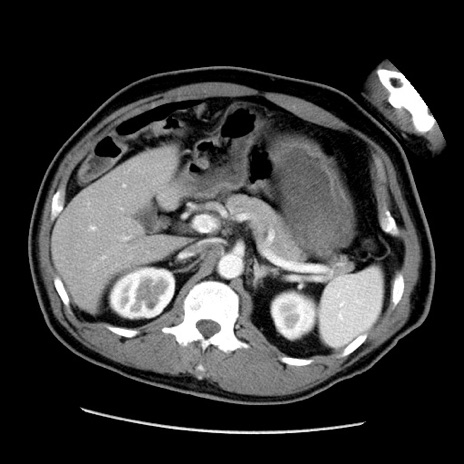

症例22(横断像)

【症例】50歳代男性

【主訴】腹痛

【現病歴】AVMからの被殻出血のため回復期リハ病棟入院中。 本日午後3時頃急に下腹部痛が出現した。

【既往歴】AVM、被殻出血、虫垂炎、高血圧

【身体所見】意識晴明、左半身不全麻痺、会話の理解は良好、36.5°C、腹部:膨隆、全体に板状硬、下腹部正中に圧痛点あり、反跳痛-、筋性防御不明、右下腹部にope scar

【データ】WBC 9400、CRP 0.06